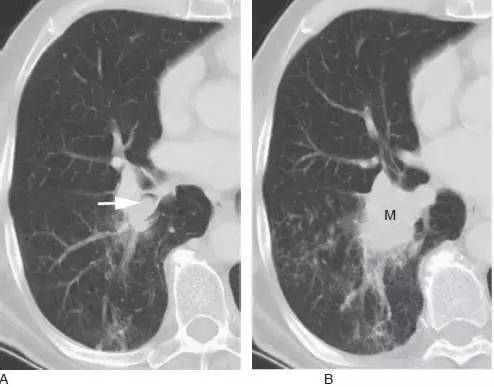

图1 表现为支气管管腔内和肺门肿块的鳞状细胞癌

A.CT 显示右下叶支气管内息肉状的肿块( 箭头),为典型的鳞状细胞癌;

B. 在稍低层面,支气管腔阻塞伴局部浸润,导致肺门肿块(M)